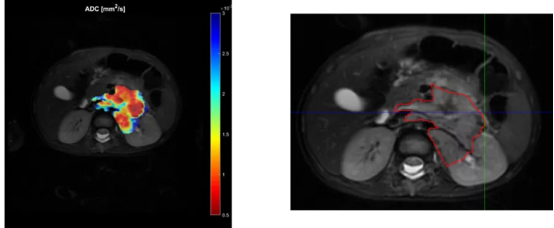

M2BE团队利用Ansys Mechanical APDL和Ansys Workbench的功能,从神经母细胞瘤扫描中提取现有的核磁共振成像(MRI)数据,并将其转换为数字模型的基础。

神经母细胞瘤的核磁共振成像(MRI)扫描

不同的MRI序列可提供身体和肿瘤生理学的详细视图。T2加权图像(T2w)显示了器官或肿瘤的几何结构。动态对比增强(DCE)成像可提供有关器官血管化的详细信息,而弥散加权成像(DWI)则可提供肿瘤细胞结构的洞察。在掌握了实验对象的这些细节后,该团队开始为他们的模型提供有效的有限元(FE)网格信息。